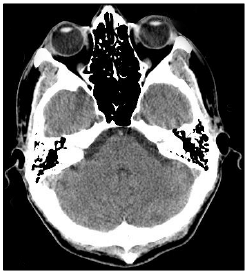

Analise a imagem de crânio a seguir.

É correto afirmar que a imagem anterior trata-se de uma:

Tomografia Computadorizada (TC), corte axial.

Tomografia Computadorizada (TC), corte coronal.

Ressonância Magnética Nuclear (RMN), corte axial.

Ressonância Magnética Nuclear (RMN), corte coronal.